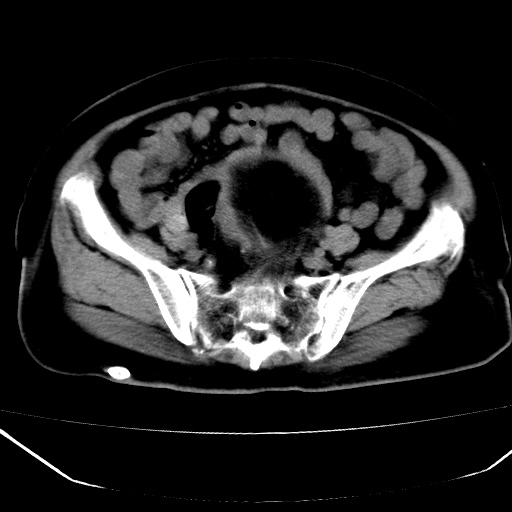

患者,女,74岁,无不适,b超示盆腔包块。

子宫前上方巨大脂性肿物,肿物边缘为较厚软组织密度影,其内缘欠光整,脂性密度中央见结节状软组织密度影“漂浮”,肿物与子宫前壁关系密切,考虑1脂肪瘤2皮样囊肿3肌瘤脂样变

膀胱是?

ct值-90hu